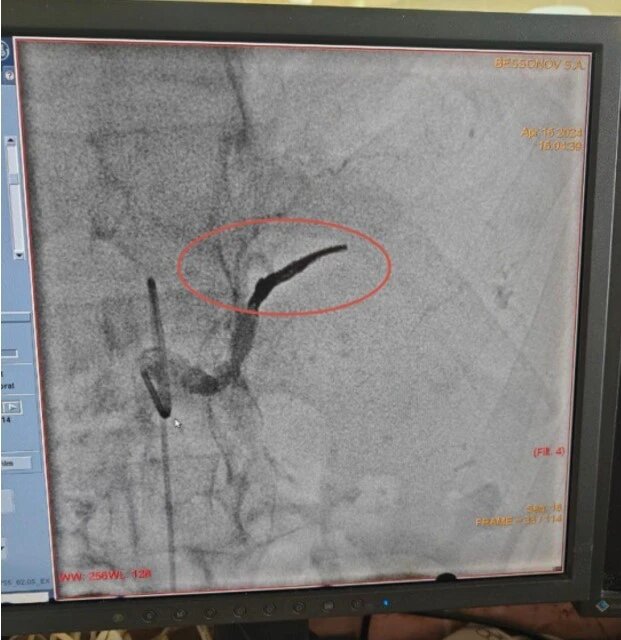

Операция на артерии длилась шесть часов

Шестичасовую операцию на крупной селезеночной артерии в минувшем году впервые в истории региона провели липецкие хирурги Владимир Анисимов и Алексей Литвиненко из областной клинической больницы. Им нужно было

купировать внутреннее кровотечение из крупной селезёночной артерии и спасти человека.

На хирургический стол попал 52-летний мужчина с обострением хронического заболевания. Но уже во время операции выяснилось, что тяжелый воспалительный процесс в поджелудочной железе разъел стенку сосуда и спровоцировал сильное внутреннее кровотечение. Пациент мог умереть в любую секунду.

Однако благодаря хирургам этого не случилось, мужчину удалось спасти.